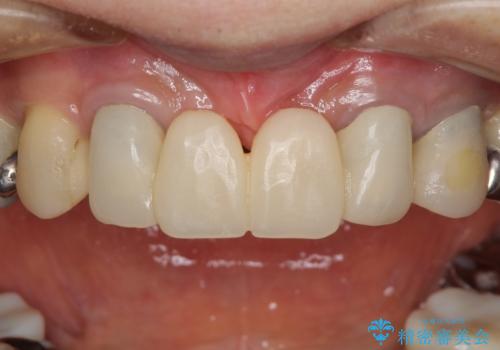

話しにくく腫れやすい前歯のブリッジ 使用感の良いオールセラミックブリッジに

- 矯正治療を行った歯科医院で装着した前歯の仮歯が不快とのことで来院された患者様です。

仮歯自体はとても綺麗でしたが、2本の歯が欠損している部分に上唇小帯が入り込んでいたため、歯肉形成を行った上で仮歯を調整し、オールセラミックブリッジを装着することとしました。